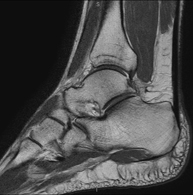

- RM Tobillo

Exploración para el estudio de la articulación y sus frecuentes lesiones de ligamentos (esguinces) así como de la afectación de otras estructuras como el cartílago o el hueso. También es de gran utilidad para diagnosticar alteraciones en el tendón de Aquiles (tendinitis, roturas). Duración de aproximadamente 20 minutos. No emplea radiación ionizante.